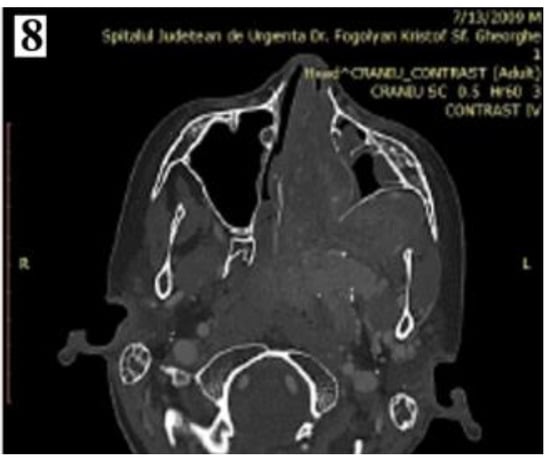

Figure 1.

Smooth, lobulated, pale or grey-red, intensely congestive, compressible mass (part 1).